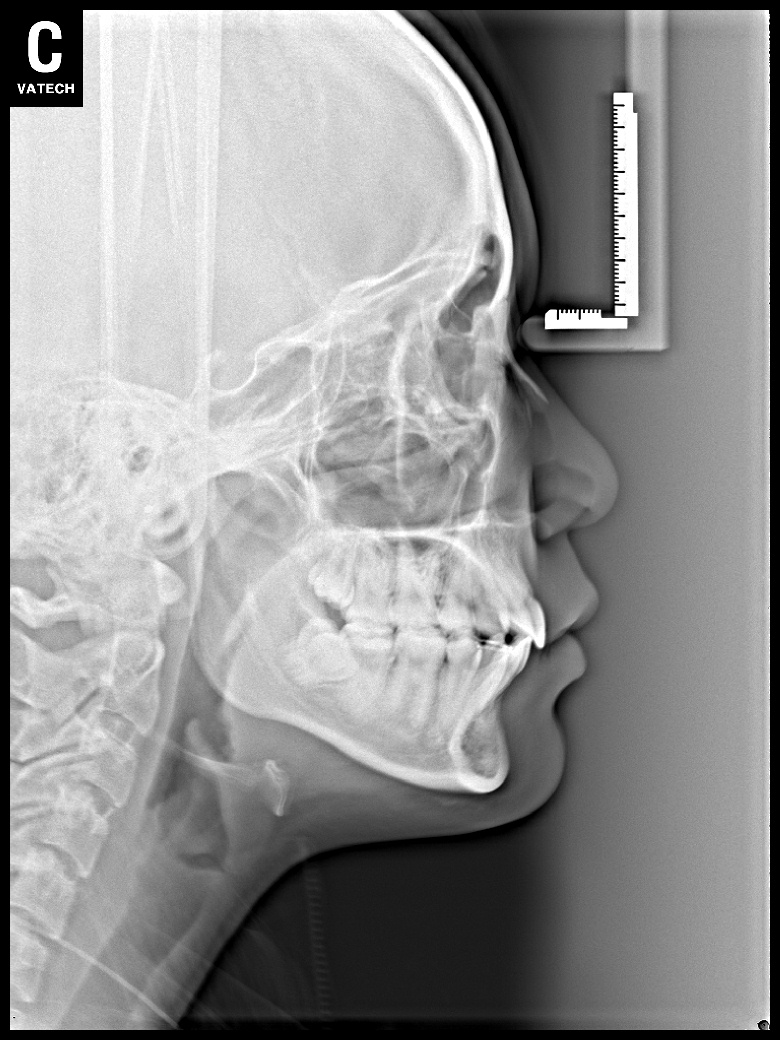

치료 전 사진입니다.